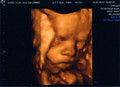

Krümmel bei der Nackenfaltenmessung, SSL 48,4 mm, man konnte schon richtig schön die Gesichtsform erkennen, vorallem die Stupsnase :-), Nackenfalte ist 1mm also unauffällig.